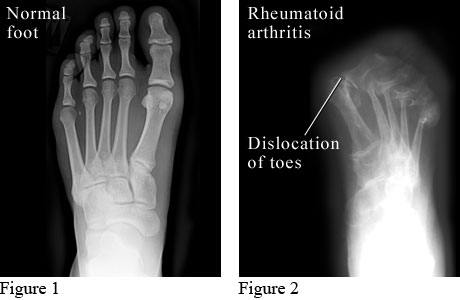

X-Ray of Rheumatoid Arthritis in the Feet

X-ray images of a normal foot and a foot with rheumatoid arthritis

The X-ray on the left shows a normal foot.

The X-ray on the right shows a foot with advanced rheumatoid arthritis. Cartilage and bone are worn away, and the bones of the toes have moved out of their normal positions.